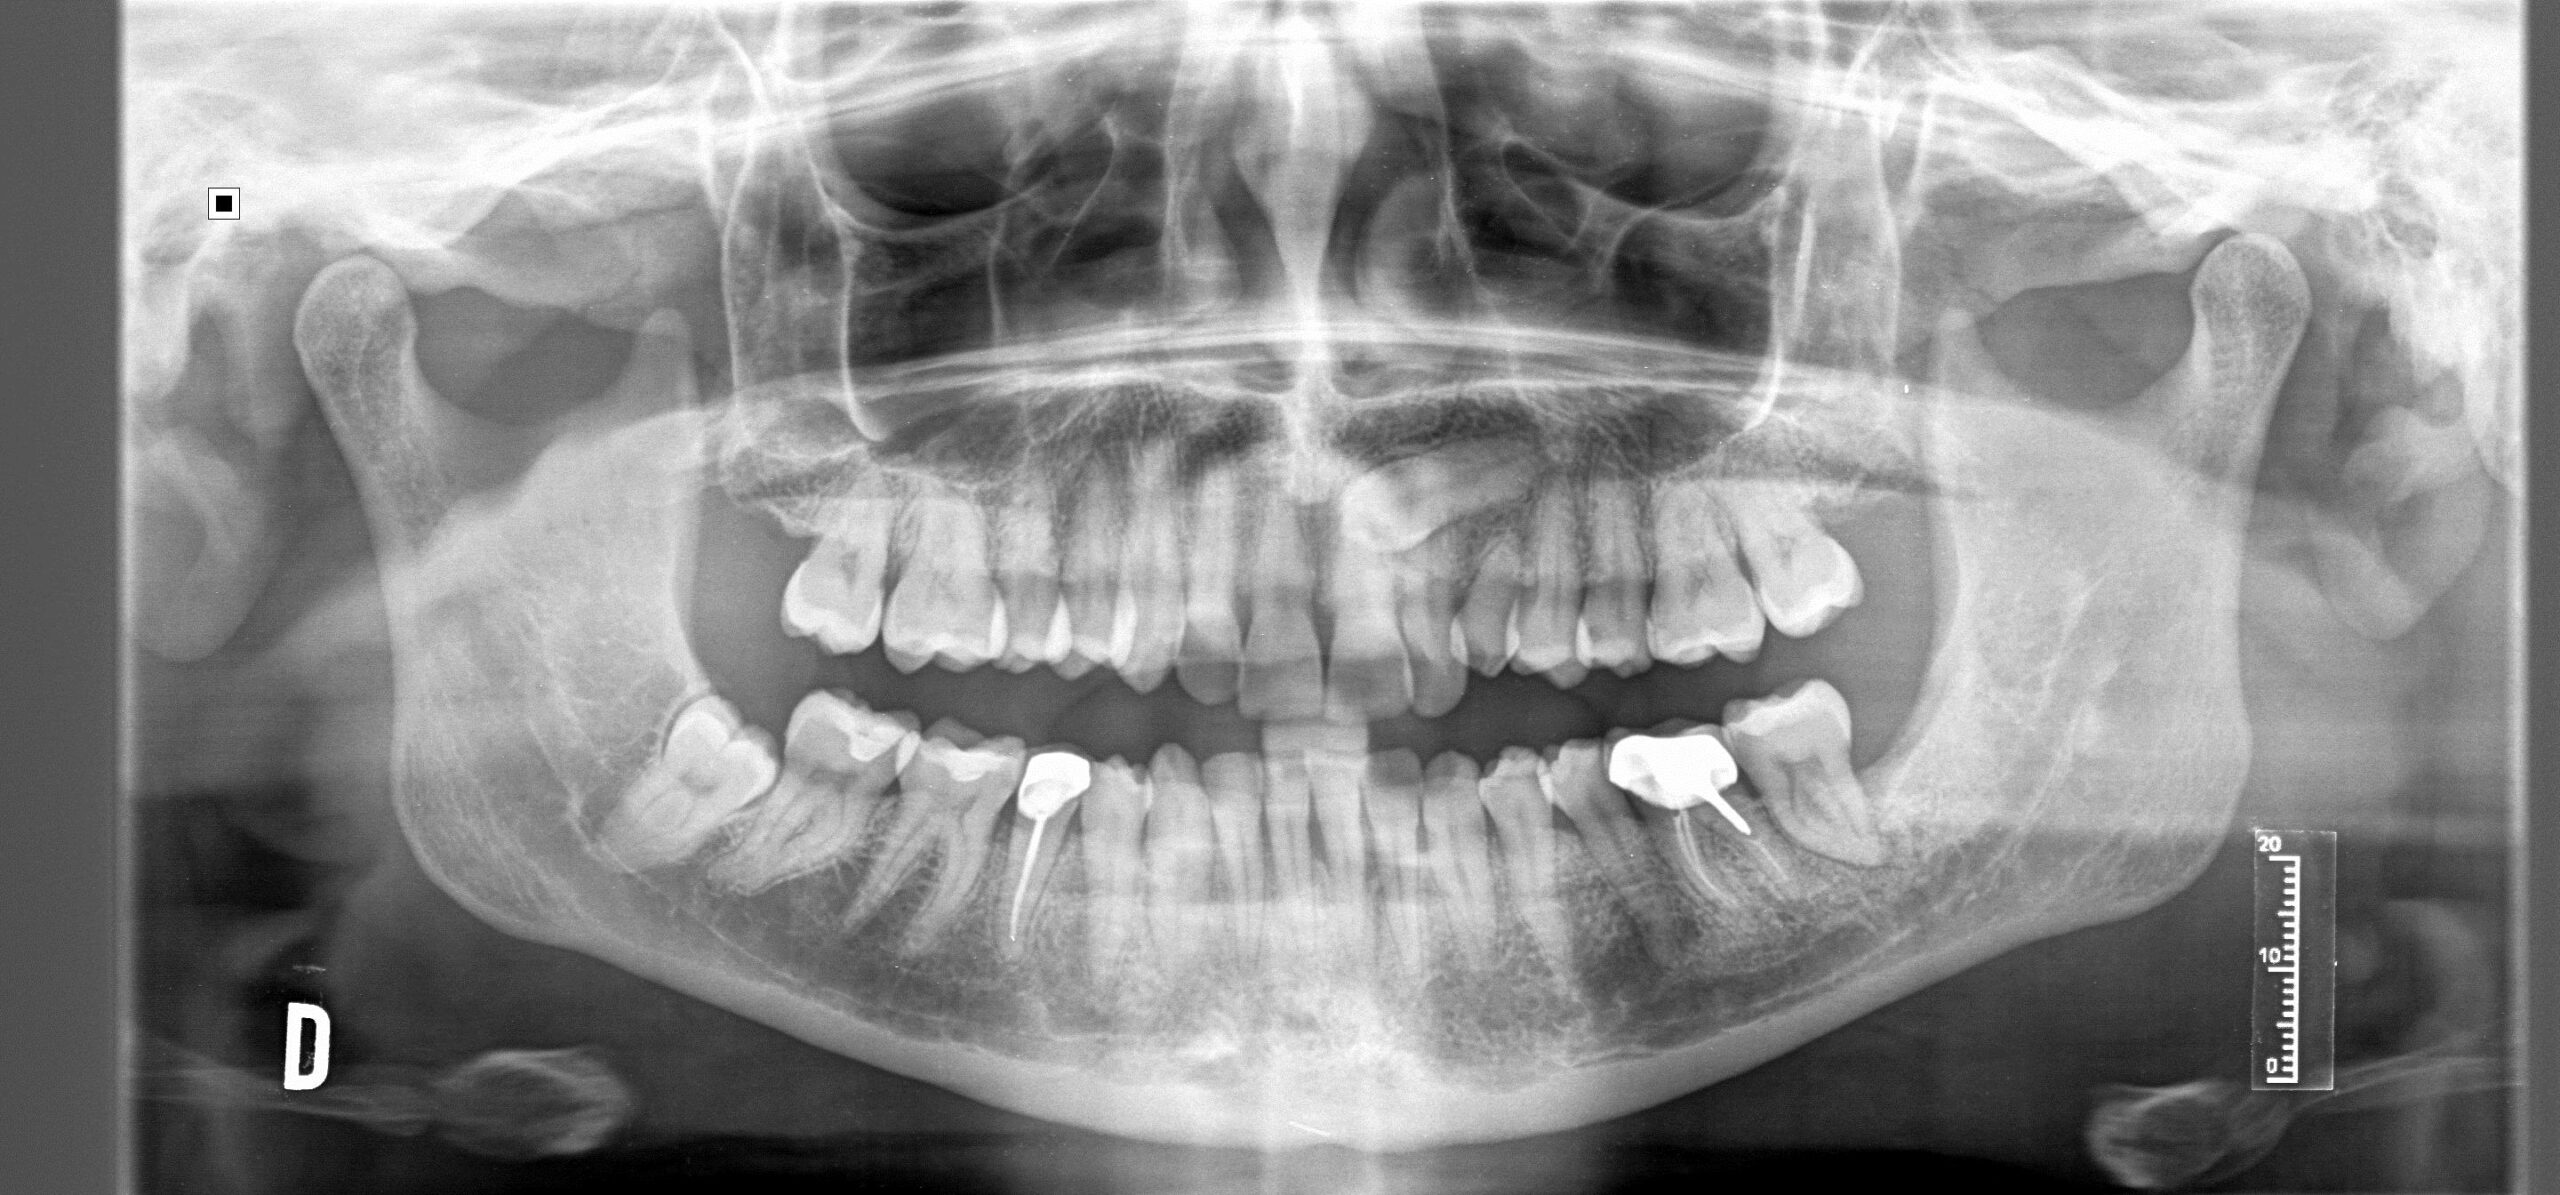

Caninos Incluidos

Son dientes que no han terminado de salir en la cavidad oral y quedan retenidos dentro del hueso en el paladar o por encima de otros dientes.

Haciendo espacio si es necesario mediante aparatos: ortopedia, brackets o alineadores. En la mayoría de los casos es necesario un TAC o CBCT ( radiografia en tres dimensiones) para localizar el diente. Posteriormente se realiza una cirugía para exponer el diente y poder llevarlo a su sitio en el arco dental con aparato de ortodoncia. Hay otras opciones de tratamiento que deben ser evaluadas por tu ortodoncista y tu cirujano dental.